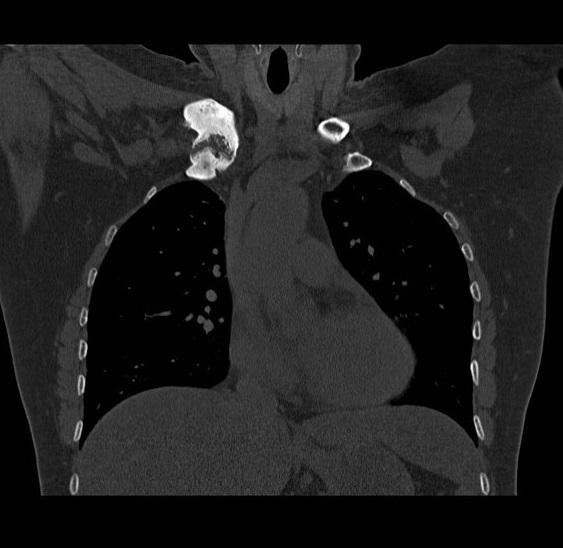

Même cas en coupe TDM coronal

( frontal ) avec image de

oedème de la moelle

osseuse dans sous-chondral gauche et élargissement et

épaississement du cartilage de articulation manubrium -costale

gauche etr en vue très nette |